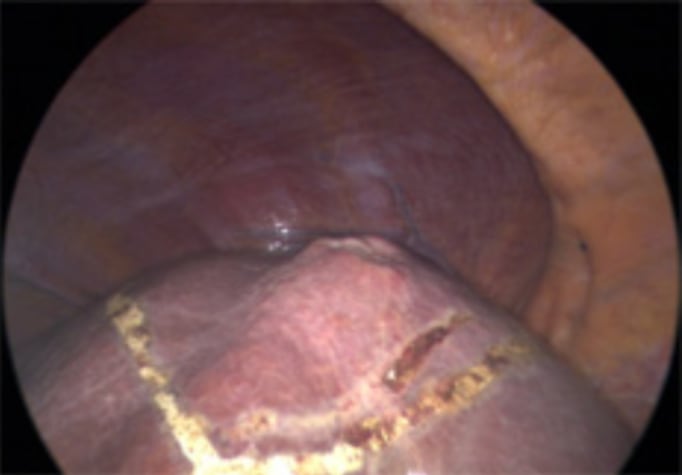

Picture showing large tear in right hepatic vein. The patient was positioned in semiprone. CVP during parenchymal transection was 8. Although CVP was relatively high, blood loss was minimal giving the surgeon time to suture the venous tear.